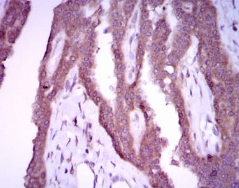

NOS2 Mouse Monoclonal antibody[4E5F3]

AC3005 NOS2 Mouse Monoclonal antibody[4E5F3] 100ug $367 10days

IHC    1/200 - 1/1000